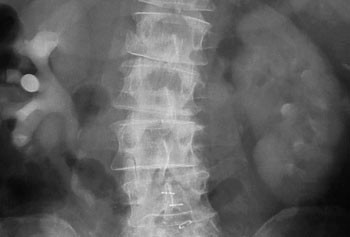

Begrunnelsen for å følge opp pasientene med røntgenurografi de første månedene etter operasjonen er å påvise passasjehinder som kan skade nyrene (fig 1 – 3). Vi fant lett utvidelse hos over halvparten av pasientene som ble undersøkt innen seks måneder etter operasjon. Dette er i samsvar med en studie av Thoeny og medarbeidere, der utvidelse forekom i 80 % av tilfellene. I deres studie var imidlertid alle grader av utvidelse tatt med og kun pasienter med ortotopisk blæresubstitutt var inkludert, mens vi tok med pasienter med ulike typer urinavledning.